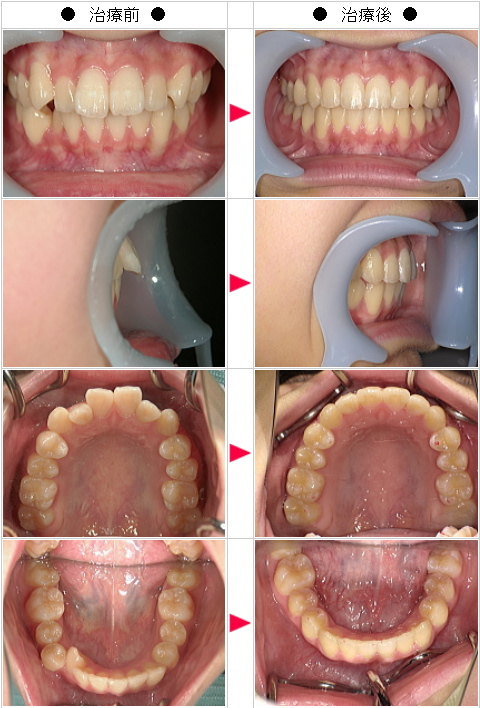

【インビザライン】出っ歯矯正の治療症例解説--全体矯正--

☆出っ歯矯正の治療症例[美絵様 32歳 女性]

-インビザライン・マウスピース矯正 治療症例解説